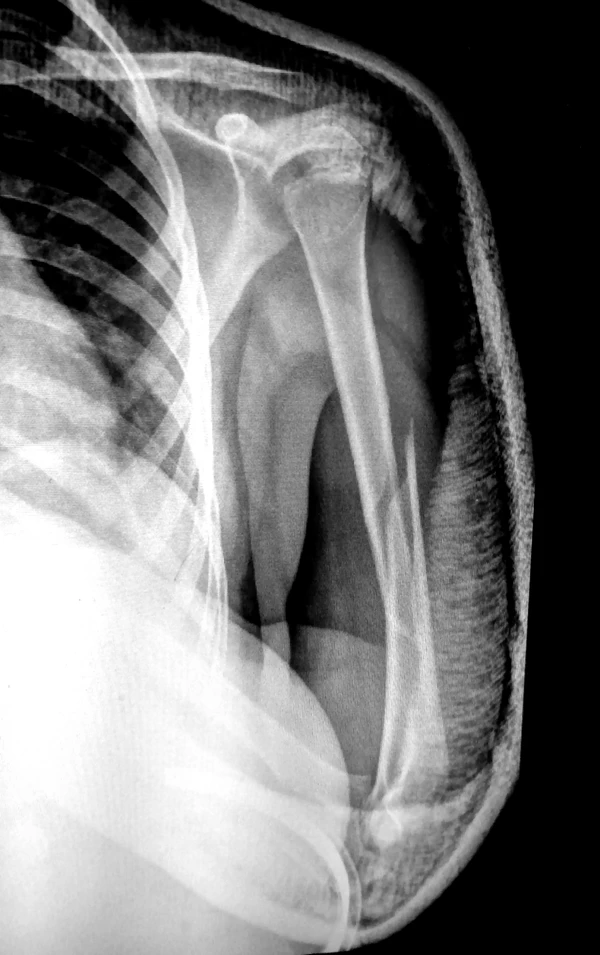

Рентгенограмма при диафизарном переломе плеча. Переломы плеча в среднем отделе (диафизарные переломы плеча) возникают в результате падения на руку или удара по плечу, могут быть косыми, поперечными, винтообразными и оскольчатыми. Диафизарные переломы плеча нередко сочетаются с повреждением лучевого нерва. Возможно повреждение плечевых артерий и вен.

- Симптомы

Клиническими признаками перелома плеча являются боли, отёчность, деформация, крепитация костных фрагментов и патологическая подвижность плечевой кости. При переломах плеча с повреждением лучевого нерва пациент не может самостоятельно разогнуть пальцы и кисть. Для уточнения диагноза и выбора тактики лечения выполняют рентгенографическое исследование.

- Лечение

Переломы плеча без смещения фиксируют гипсовой лангетой, с последующей её заменой на закрытую повязку типа «Дезо» или «Вильпо». При этом контролируется сопоставление отломков с помощью рентгенограмм в разных проекциях. Общий срок иммобилизации при консервативном лечении диафизарных переломов плечевой кости составляет 3—3,5 месяца.

Консервативное лечение целесообразно только в редких случаях: при переломах без смещения или при минимальном смещении отломков, а также при возникновении противопоказаний к операции. В остальных случаях показано оперативное лечение, так как современные малоинвазивные и другие методы фиксации позволяют уже через 3-4 недели начинать разработку движений в плечевом и локтевом суставах, что в свою очередь, предупреждает возникновение тяжёлых контрактур в этих суставах. При повреждении лучевого нерва вследствие перелома проводят оперативное лечение с обязательной ревизией нерва, с адекватной фиксацией отломков.

Хирургическое лечение также показано при многооскольчатых переломах плеча, невозможности закрытой репозиции, интерпозиции мягких тканей и повреждении сосудов и нервов. Фиксацию отломков осуществляют при помощи пластин, интрамедуллярных штифтов с блокированием, или аппарата Илизарова.